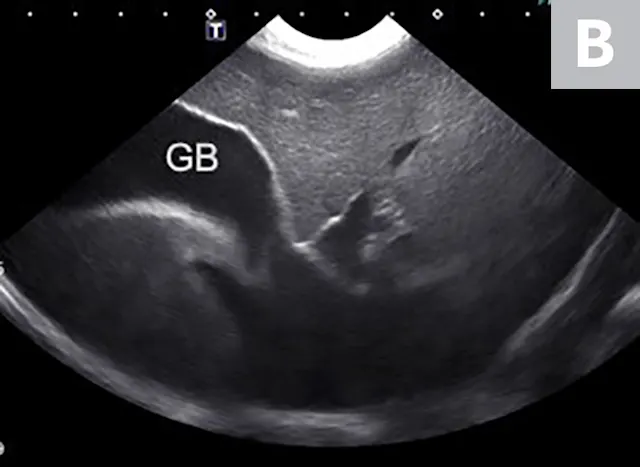

Imaging of a 1-year-old neutered male standard poodle presented with anorexia, lethargy, vomiting, hypoalbuminemia, hypoproteinemia, and cranial abdominal organomegaly. Transverse (A) and sagittal (B) ultrasound of the liver and gallbladder (GB). The liver is enlarged (with increased distance off the stomach from the diaphragm, rounded borders, and extension ventral to the stomach), diffusely hyperechoic, and homogenous. The gallbladder is moderately distended with a normal wall and content. Radiographs demonstrate hepatomegaly and splenomegaly (C). Abdominal ultrasound images revealed splenic enlargement with a mildly mottled architecture and a solitary hypoechoic nodule (D; arrowheads). The pancreas is enlarged and lobulated with multiple hypoechoic tracts and a peripheral capsule (E; between electronic cursors [X’s]). The jejunal lymph nodes are severely enlarged (F; between electronic cursors [X’s]), more than expected for a young dog. The combination of severe hepatosplenomegaly and lymphadenomegaly make systemic disease (eg, infectious, neoplastic) most likely. The appearance of the pancreas is due to pancreatic edema secondary to hypoproteinemia. Acute liver injury was diagnosed, and lymphoma was diagnosed based on hepatic and splenic cytology.